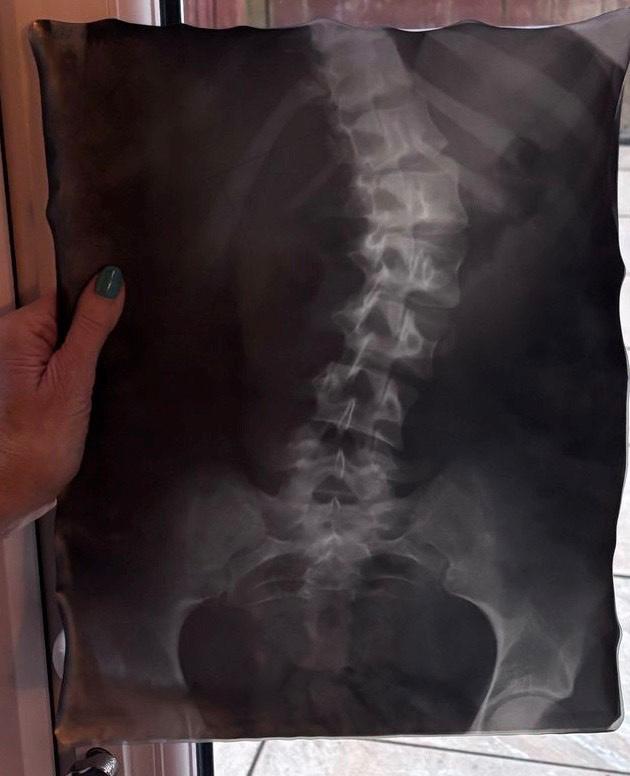

With a referral in hand, we returned to the doctor, and X-rays confirmed a 44-degree spinal curve. The consultant recommended a back brace, explaining that while it wouldn’t straighten her spine, it could help prevent further progression. Pixie was fitted for her brace and chose a pink design—a small but meaningful choice that made the experience a little brighter. She playfully teased me about what I would have chosen—a multicoloured leopard print!

3 months later, a follow-up X-ray brought incredible news—the brace had already helped correct her spine by 10 degrees. After 9 months, another out-of-brace X-ray showed further improvement, reducing the curve to 35 degrees. Seeing these results motivated Pixie to continue wearing the brace with dedication.

In November 1979, X-rays showed my top curve had reduced from 84 to 64 degrees, and my bottom curve from 74 to 60.